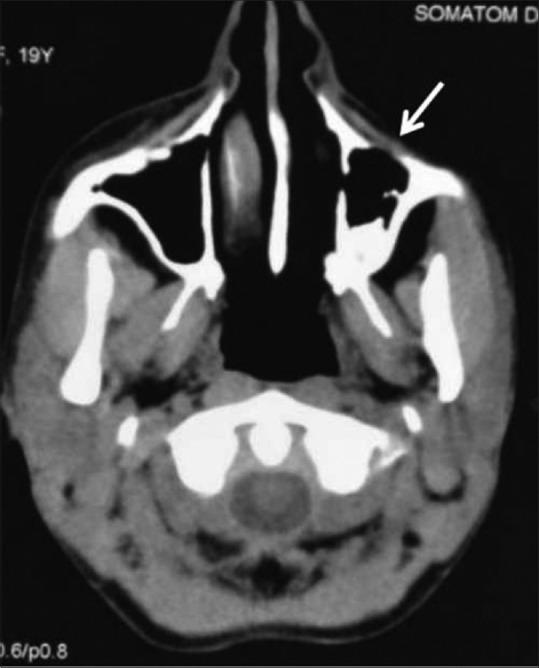

phakomatoses:图文综述。

Phakomatoses: A pictorial review.

Phakomatoses or Neurocutaneous syndromes are a heterogeneous group of disorders and have variable inheritance pattern. Currently, more than 30 entities are included in this group. These disorders primarily affect the central nervous system; however, skin, viscera, and other connective tissues can also be involved with variable clinical presentation. We will describe and illustrate the various radiological findings of the common entities through the iconography of the cases presented to our department.

摘要

phakomatoses或神经皮肤综合征是一组异质性疾病,具有可变的遗传模式。目前,该组包括30多种疾病。这些疾病主要影响中枢神经系统;然而,皮肤、内脏和其他结缔组织也可能受累,临床表现各异。我们将通过提交至我科病例的影像学表现来描述和说明常见疾病的各种放射学表现。